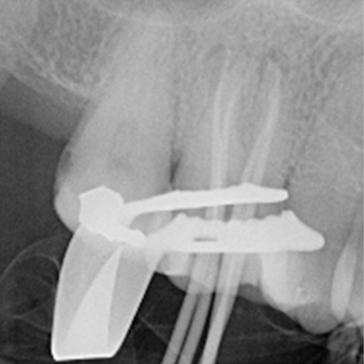

Case 2. RCT of UL6